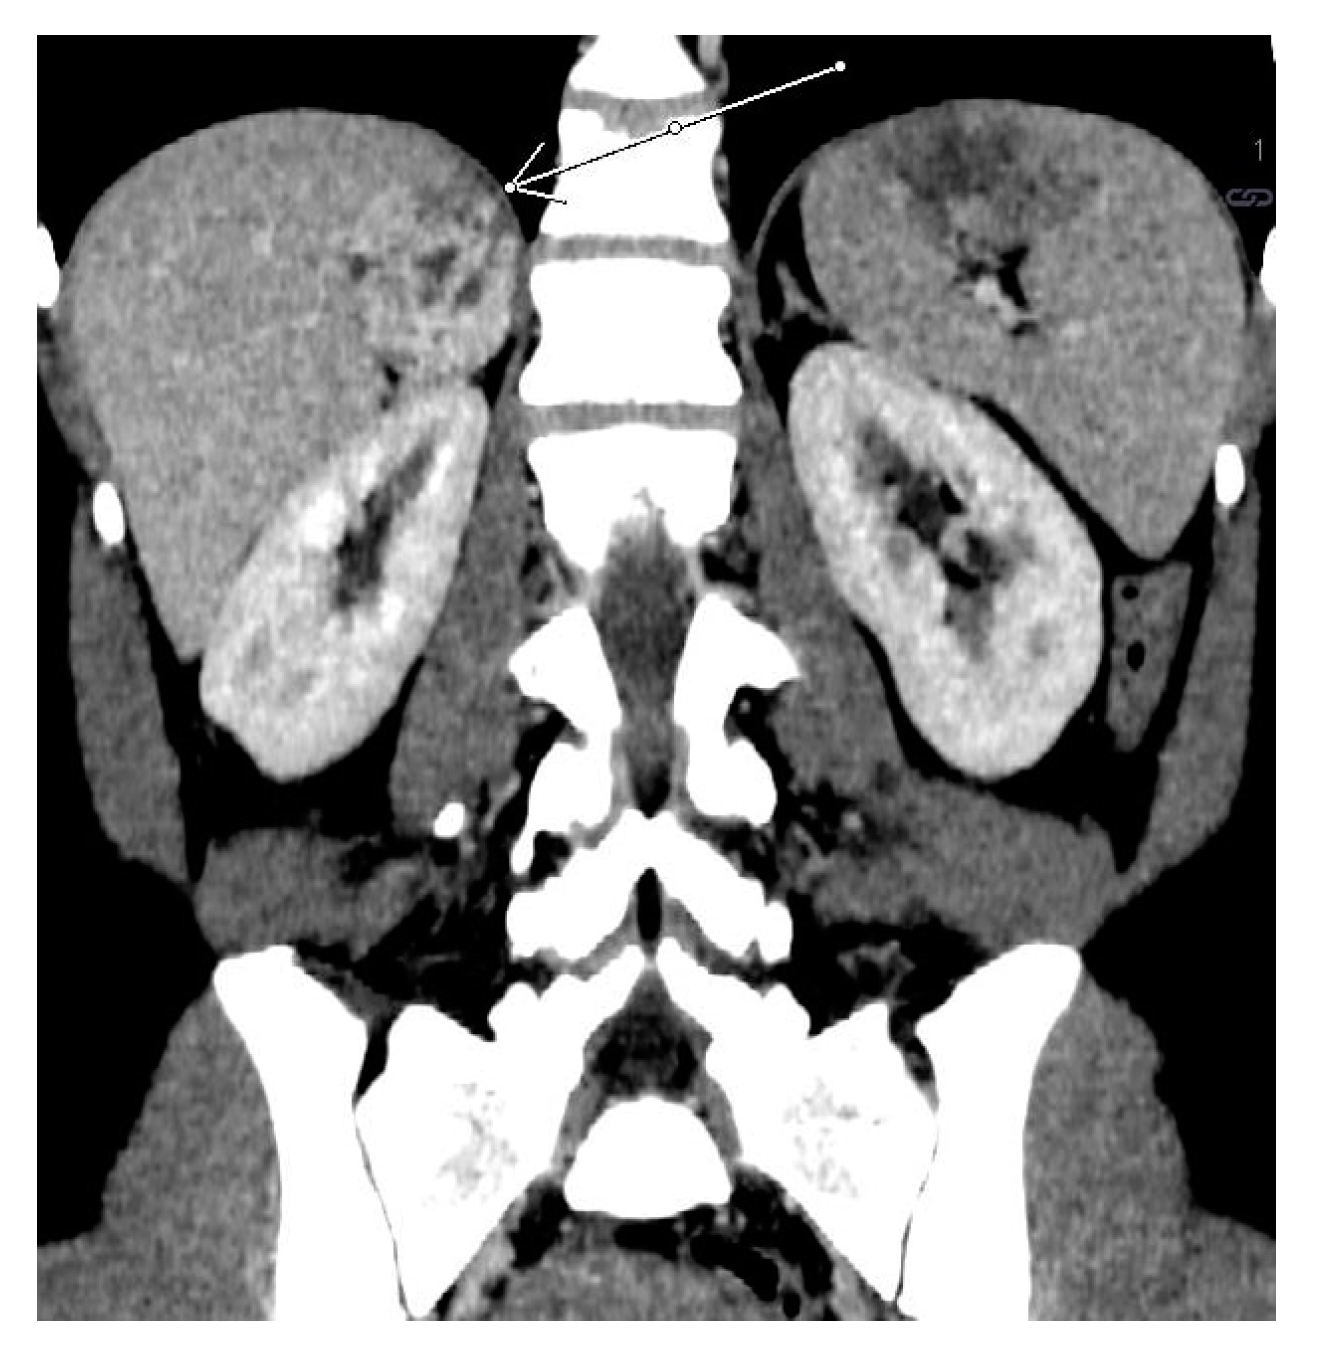

2.2. Case 2